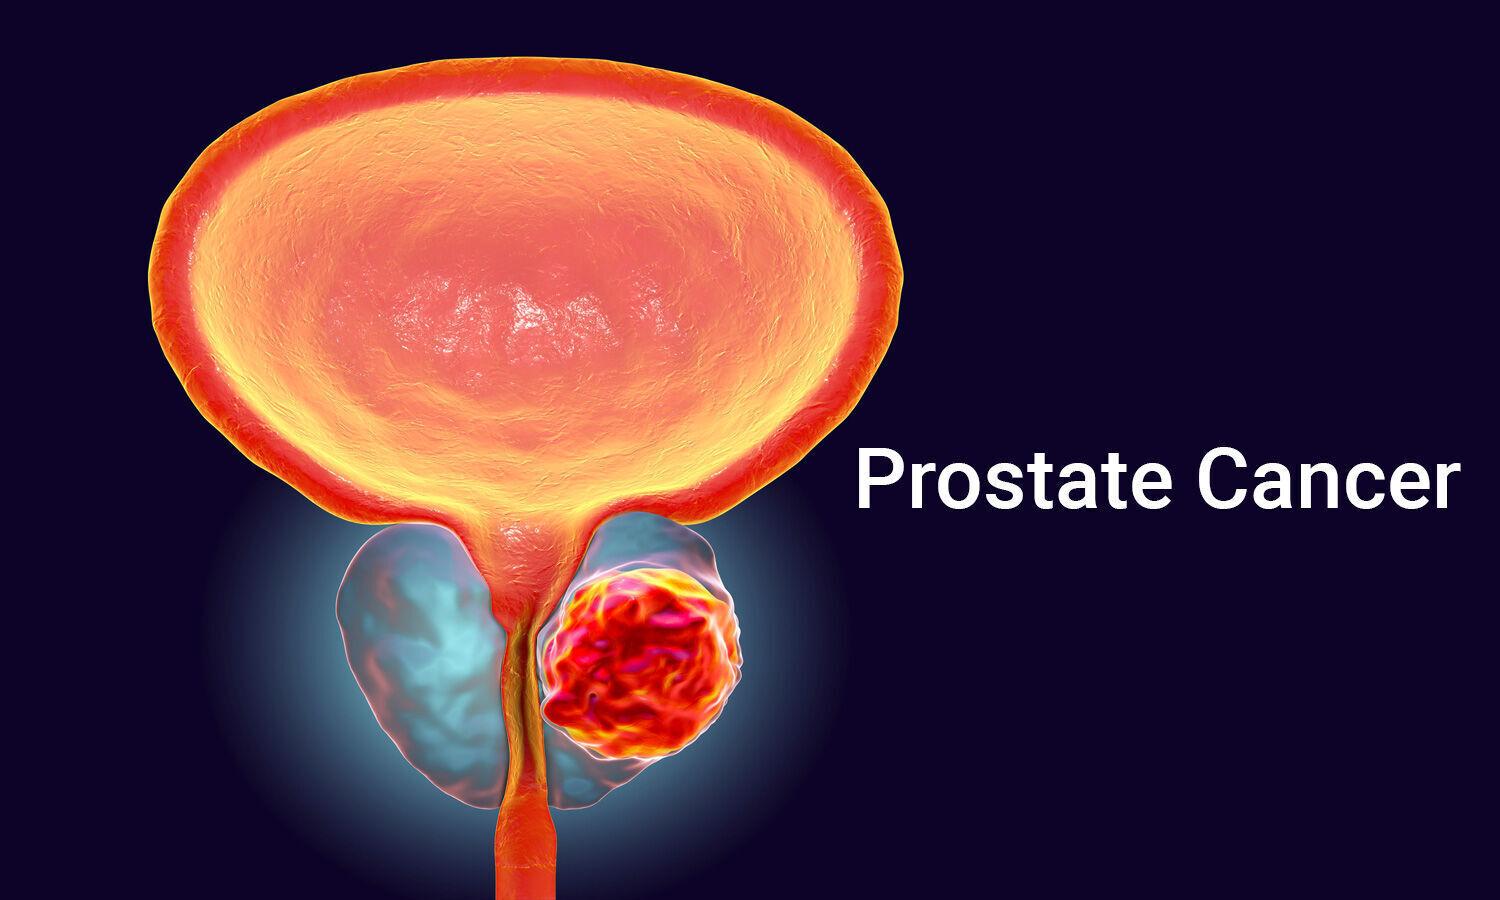

The Metastatic Prostate Cancer Market encompasses a range of advanced therapeutics designed to treat prostate tumors that have spread beyond the prostate gland. Products include novel androgen receptor inhibitors, immuno-oncology approaches, radioligand therapies, and combination regimens that enhance survival rates and quality of life. These treatments offer targeted mechanisms of action, reduced systemic toxicity, and improved patient compliance compared to traditional chemotherapy.

The growing need for effective interventions is fueled by rising prostate cancer incidence, unmet clinical needs in resistant cases, and an aging population. Continuous market research and insights into tumor biology have led to robust clinical pipelines and strategic collaborations among market companies. With increasing investments in R&D, biopharmaceutical firms are accelerating approvals and expanding indications. Enhanced diagnostic tools and personalized medicine approaches further support early detection and tailored treatment plans. As key market trends evolve, stakeholders focus on Metastatic Prostate Cancer Market growth strategies, diversifying portfolios to capture incremental market share and unlock new market opportunities.

The Global Metastatic Prostate Cancer Market is estimated to be valued at USD 12.80 Bn in 2025 and is expected to reach USD 22.51 Bn by 2032, growing at a compound annual growth rate (CAGR) of 8.4% from 2025 to 2032.

These market players have been instrumental in driving market dynamics through strategic alliances, licensing deals, and multi-center clinical trials. Leveraging market research and comprehensive market analysis, they are securing intellectual property, scaling production capabilities, and optimizing supply chains. Their diverse portfolios, including next-generation inhibitors and novel biotherapeutics, contribute substantially to global industry size and business growth. Collaborative efforts with academic institutions and contract research organizations further strengthen R&D pipelines and expedite regulatory submissions.

Rising demand for effective metastatic prostate cancer treatments is spurring market growth. Increasing patient awareness, coupled with improved screening protocols, has expanded the diagnosed population requiring therapy. Personalized medicine and biomarker-driven approaches are creating market opportunities for precision-targeted drugs. Payers and healthcare providers are recognizing the long-term benefits of early intervention, which drives reimbursement approvals. Continuous monitoring of market trends reveals a shift toward combination regimens to overcome resistance, boosting average treatment durations and revenue per patient. Enhanced patient advocacy and disease-specific foundations also play a pivotal role in educating clinicians and patients about novel treatment options.